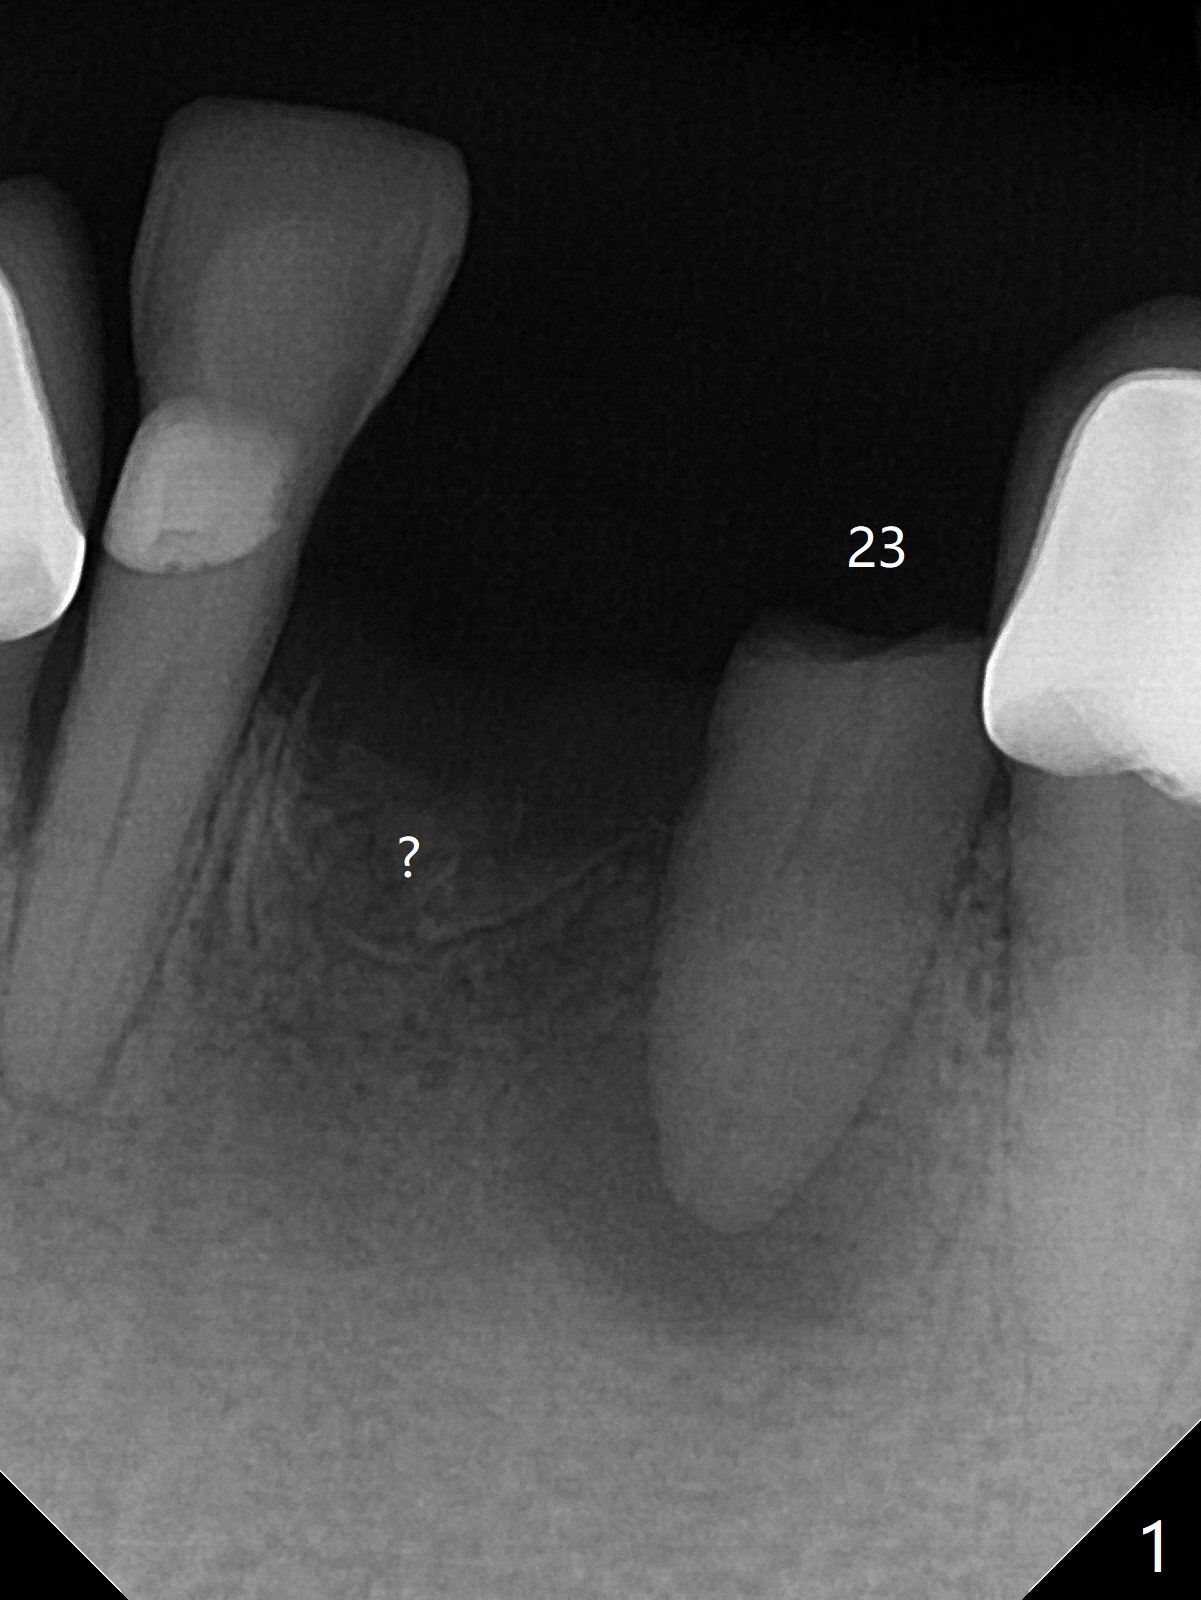

A 64-year-old woman requests extraction of the tooth #23 for lower partial (Fig.1). Since there are 2 buccal sinus tracks, another residual root is suspected (?). After shown loss of the buccal plate (Fig.2,3), the patient agrees to have socket preservation with allograft (Fig.5,6 *) and BioXclude (Fig.4 >). The suspected residual root is not explored considering the 2 sinus tracks being associated with the lesion of #23 (Fig.2,3). Cytoplast is not used because of time constraint and fear of gingival dehiscence associated with extensive dissection. In fact the sinus tracks shrink in a week, while the buccal plate remains bulging (Fig.7 *) and the socket heals (Fig.8 >). The buccal plate is flat (no swelling) 1 month postop (Fig.9).